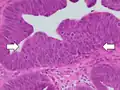

Normal (left) versus dysplastic (large at right) colonic crypts, the latter conferring a diagnosis of a tubular and/or villous adenoma. -

Histopathology of high-grade dysplasia in a tubulovillous adenoma, in this case seen mainly as loss of cell polarity, as cells become more plump and haphazard than the elongated and parallel nuclei of surrounding low-grade dysplasia.